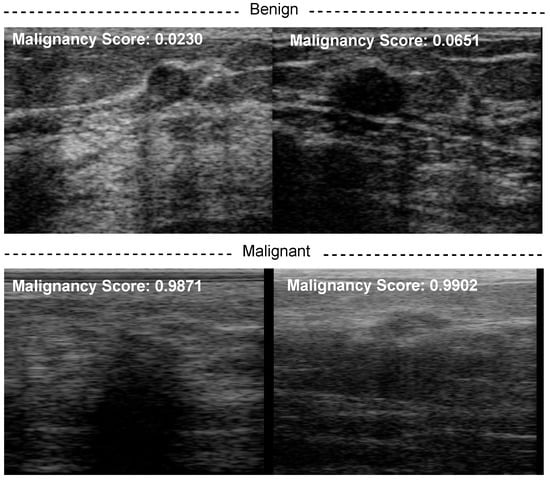

Figure 1 presents some BUS images of benign and malignant tumors. As shown, it is challenging to analyze breast tumors in BUS images due to their low contrast, poor signal-to-noise ratio (SNR), the great shape variety of breast tumors, and the hazy nature of BUS images. Tumor segmentation and classification are two crucial tasks in CAD systems. Benign and malignant tumors usually display different visual characteristics in BUS images. The margins of most benign tumors are smooth, round, or oval, but the borders of most malignant tumors are irregular and spiculated [6]. Nevertheless, designing CAD systems for BUS is still challenging due to the large variation in tumor size and shape, ambiguous tumor boundaries, and low SNR.

Figure 1. Examples of BUS images for (a,b) benign and (c,d) malignant cases. They show the presence of artifacts such as speckle noise and the hypoechoic region with shadows caused by the reflection of a high quantity of energy by an enormous impedance discontinuity and a variety of breast tumor shapes and sizes.

Deep learning has improved the automated analysis of BUS images in the last decade, thanks to its ability to extract powerful representations from them. Hence, several deep-learning-based CAD systems have been proposed to detect breast cancer or discriminate between benign and malignant tumors [7]. For instance, Masud et al. [8] used ultrasound images to develop and assess three pretrained convolutional neural network (CNN)-based models for recognizing breast cancer. The authors tweaked AlexNet [9], DenseNet121 [10], MobileNetV2 [11], ResNet-18 [12], ResNet-50 [12], VGG16 [13], and Xception’s [14] pretrained models to extract powerful representative features from BUS and to add a classifier to the top layer. Most existing studies employ a single ultrasound image (SUI) for each breast tumor to extract features to discriminate between benign and malignant tumors. However, artifacts in BUS images such as speckle noise and shadows (as shown in Figure 1) may degrade the performance of feature extraction methods. Unlike most existing SUI-based studies, we propose to use deep-learning-based radiomic features extracted from BUS sequences in this paper. Specifically, we employ the ConvNeXt [15] network, which is a CNN trained using the vision transformer style. The proposed approach contains three main components: radiomic features extraction based on ConvNeXt, malignancy score pooling mechanism, and visual interpretations.